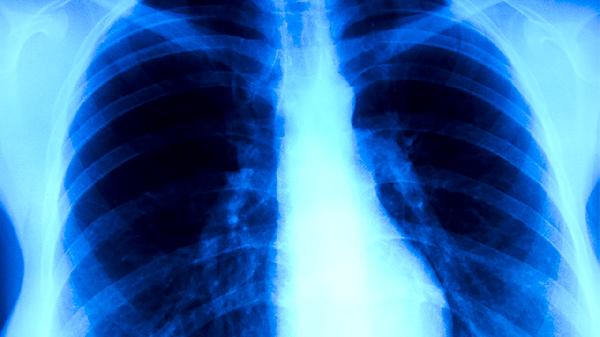

肿瘤患者应定期复查影像学及肿瘤标志物,在医生指导下综合运用手术、放化疗、靶向治疗等现代医学手段。保持高蛋白饮食如鱼肉蛋奶,适当补充维生素C和维生素B族,避免辛辣刺激食物。建议进行八段锦、散步等低强度运动,每日保证7-8小时睡眠,通过正念冥想缓解焦虑情绪。